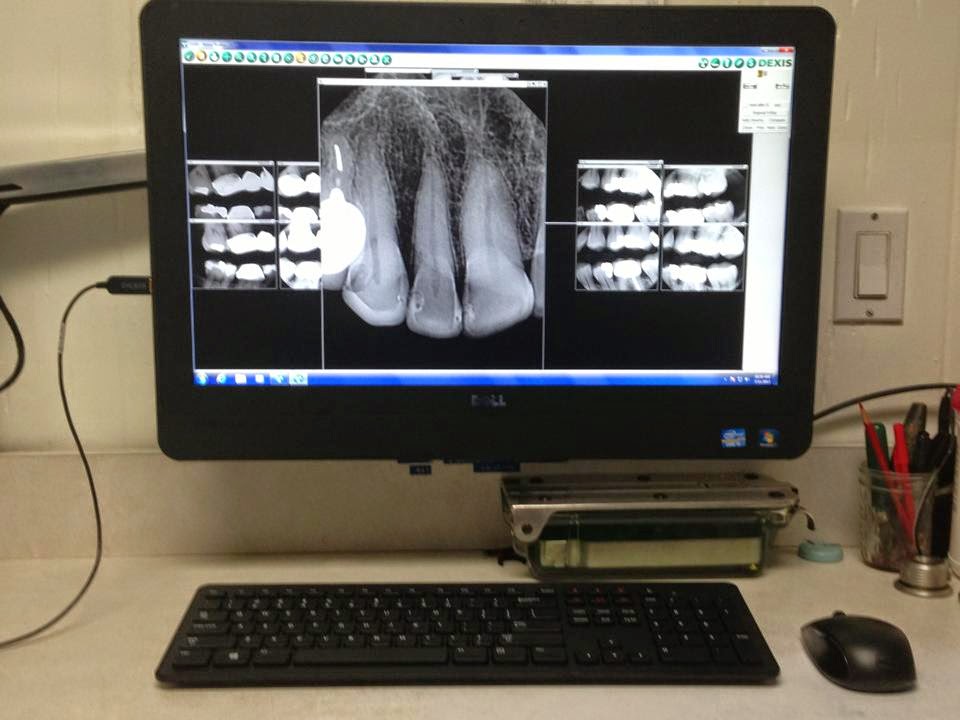

The history of the practice is rooted in Dr. Spindel's extensive education and passion for continuous learning. After earning his dental degree, he pursued advanced specialty training in prosthodontics, the dental field pertaining to the diagnosis, treatment planning, rehabilitation, and maintenance of oral function, comfort, appearance, and health of patients with clinical conditions associated with missing or deficient teeth and/or oral and maxillofacial tissues. This rigorous specialty training forms the bedrock of his expertise, setting his practice apart from general dentistry offices. Since establishing his practice, Dr. Spindel has dedicated himself to staying at the forefront of dental technology and techniques, integrating digital imaging, CAD/CAM technology, and advanced materials to provide predictable, long-lasting, and beautiful results.